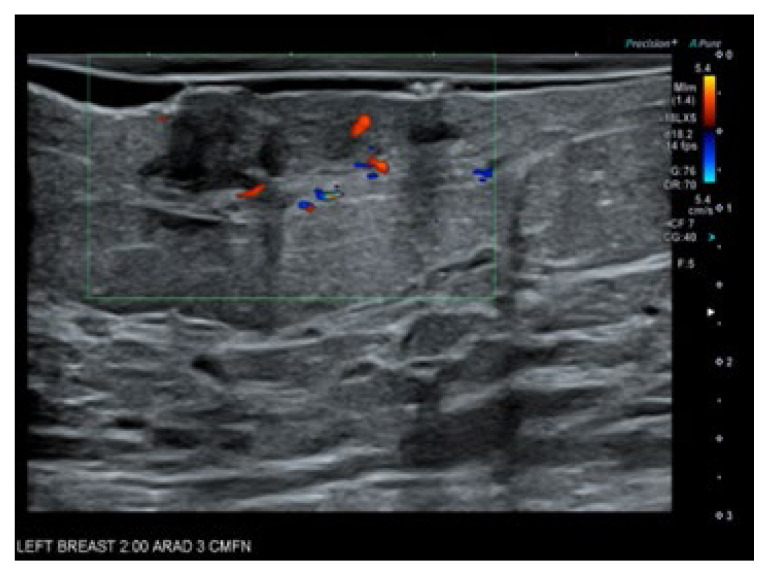

Recurrent Breast Angiosarcoma.

复发性乳腺血管肉瘤